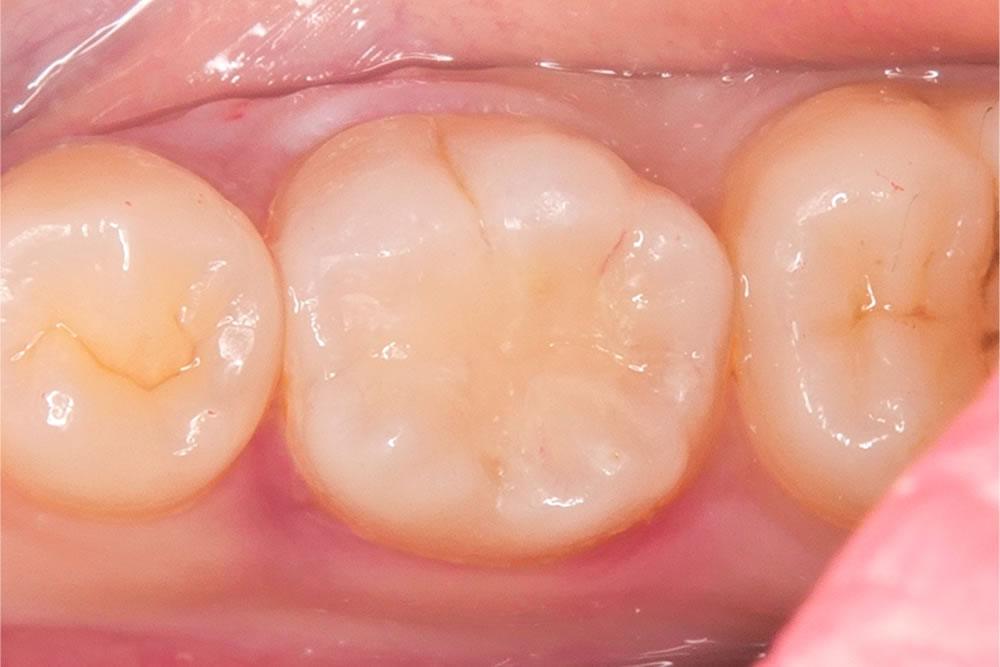

こちらの患者さまは、右下奥歯の虫歯を主訴に来院されました。

右下の奥歯に黒い部分が見受けられます。範囲は小さいため、出来るだけ削らないように先端の小さな器具を用いて丁寧に虫歯を除去していきます。

う蝕検知液を用いて丁寧に虫歯を取り除いていきます。

さらに奥にある虫歯は、より小さな器具を用いて削る範囲が大きくなりすぎないようにします。

コンポジットレジンという樹脂の材料を用いて削った部分を埋めていきます。

形態を整えて歯の形にしていきます。

形態修正と研磨を行い、治療が終わりました。